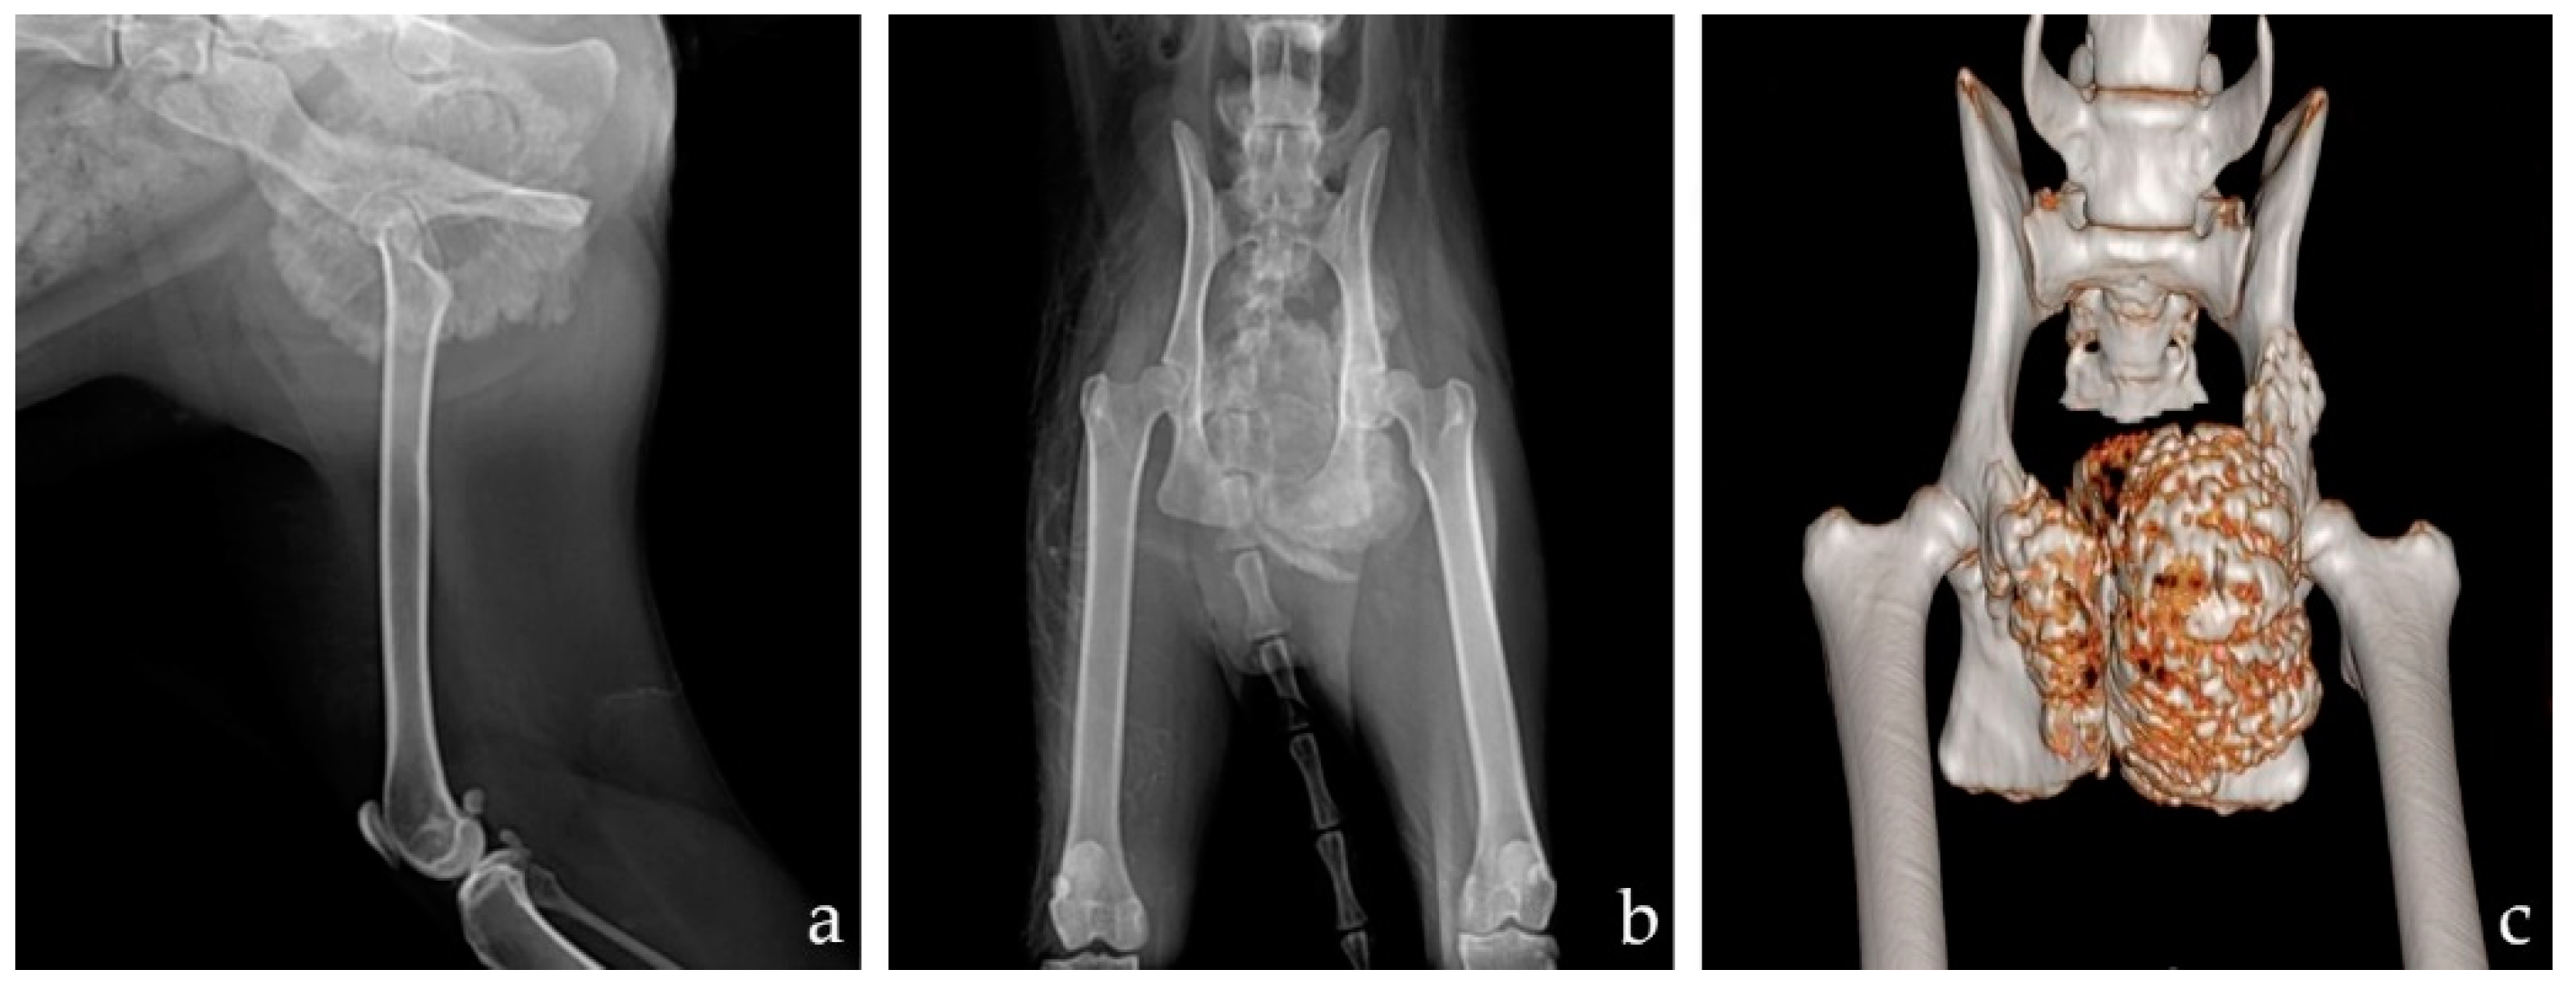

2.1. Case

2.2. Planning